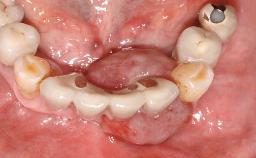

Biological complications caused by undetected cement residue have been receiving much attention. Excess cement might be responsible not only for rapidly developing of peri-implantitis, but also for delayed or chronic manifestations of the disease many years after cementation (Wilson 2009; Linkevicius and coworkers 2013). Invitro and clinical studies have shown that it is very difficult or even impossible to completely clean up excess cement at subgingival margins, so popular in cemented restorations (Agar and coworkers 1997; Linkevicius and coworkers 2011, 2012). Possible outcomes of biological complications due to excess cement range from temporary inflammation of the peri-implant soft tissues without any serious esthetic and functional consequences all the way to implant loss. This report describes a case of peri-implantitis caused by residual cement; as well as the management and quite unusual resolution of the complication. The patient presented in 2009 with a draining sinus tract, tenderness on chewing, and tissue contact above the implant-supported restoration. The implant had been restored approximately three years before.